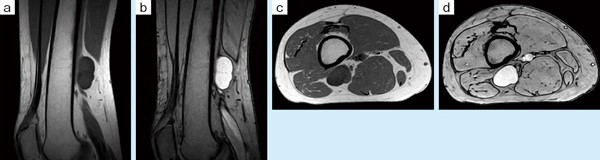

■症例1:右大腿軟部腫瘍

55歳,女性。10年前に軽い膝上部の痛みで受診。単純X線では所見がなく,触診で大腿後部に腫瘍様しこりを触れた。MRIにて軟部腫瘍を確認し,年1回のMRI検査を行っているが,サイジングにより腫瘍の拡大が確認されており,手術治療を検討している。 a:T1WI,COR,FOV:200mm,TR/TE:460/16,FA:90°,スライス厚:3mm b:T2*WI,COR,FOV:200mm,TR/TE:790/15,FA:30°,スライス厚:3mm c:T1WI,AX,FOV:200mm,TR/TE:460/16,FA:90°,スライス厚:3mm d:T2*WI,AX,FOV:200mm,TR/TE:790/15,FA:30°,スライス厚:3mm